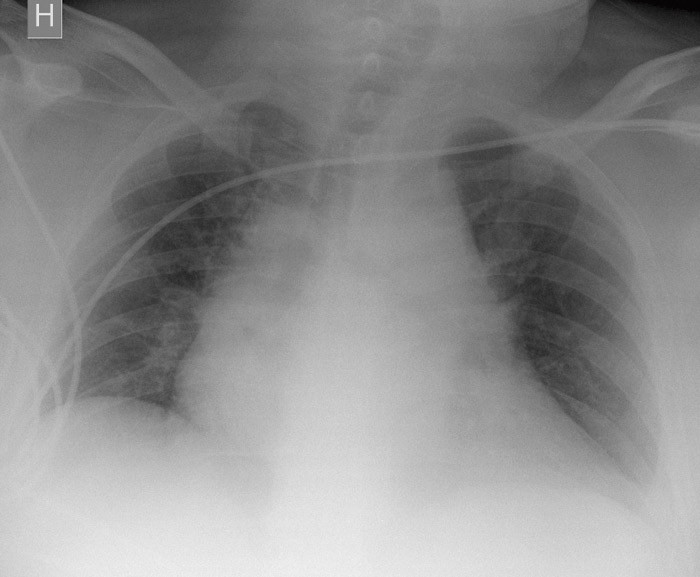

Flere diagnoser ble vurdert. Pasienten oppfylte tre av kriteriene for systemisk inflammatorisk respons-syndrom (SIRS) (puls > 90/min, temperatur < 36 °C, respirasjonsfrekvens > 20/min), og sepsis kunne ikke utelukkes. Cerebral iskemi ble vurdert, hovedsakelig grunnet uro og uklarhet, så vel som lungeemboli. Det ble gitt intravenøs væske og oksygen på maske, men pasienten tolererte ikke masken og ble tiltakende urolig. Arteriell blodgass viste pH 7,29 (7,350 – 7,450), pCO₂ 3,8 kPa (4,67 – 6,00 kPa), pO₂ 11,5 kPa (10,67 – 13,33 kPa), laktat 10,4 mmol/l (0,4 – 2,2 mmol/l) og Hb 12,6 g/100 ml (11,5 – 17,4 g/100 ml). EKG viste sinustakykardi uten iskemitegn. Pasienten var palpasjonsøm supraumbilikalt og myk i buken, men det hørtes ingen tarmlyder. Gastrokirurg så til pasienten og innkalte radiolog for ultralydundersøkelse av typen «focused assessment with sonography for trauma» (FAST). Undersøkelsen viste ingen åpenbare patologiske tegn, heller ingen perikardvæske. Røntgen thorax viste ikke hemo- eller pneumothorax, men ga mistanke om breddeforøket mediastinum (fig 1). Selv om pasienten var ustabil, ble det rekvirert CT thorax.

Det ble også mistenkt ventilatorassosiert pneumoni (VAP), og det ble startet behandling med cefuroksim intravenøst. Tredje postoperative døgn hadde CRP-nivået steget til over 300 mg/l, røntgen thorax viste bilateral sløring og bronkoskopi viste purulent slim. Man erstattet cefuroksim med piperacillin/tazobactam. Pasienten fylte kriteriene for akutt lungesviktsyndrom (ARDS) (6) og ble ventilert trykkontrollert med tanke på lungeproteksjon. Man forsøkte også mageleie – med effekt. Antibiotikabehandlingen med tanke på bakteriell pneumoni ble fortsatt.

Pasienten utviklet raskt dialysekrevende nyresvikt og det vi oppfattet som ventilatorassosiert pneumoni. Røntgenforandringene ble beskrevet som bilateral basal sløring, i tillegg til stuvning og atelektaser. Vi kan ikke utelukke at det i alle fall delvis kunne dreie seg om akutt lungeskade (acute lung injury, ALI), og på det mest akutte oppfylte han kriteriene for akutt lungesviktsyndrom. Pasienten ble tiltakende septisk med alvorlig nyresvikt, og aminoglykosidbehandling var derfor kontraindisert. Sent i forløpet ble han behandlet med meropenem, noe som nok bidro til at han ble infeksjonsfri. Meropenem er dialyserbart, har effekt mot pseudomonas og kan brukes som monoterapi ved sepsis. Hadde man startet med midlet tidligere, ville trolig tiden pasienten var septisk blitt kortet ned og multiorgansvikten kanskje mindre uttalt.